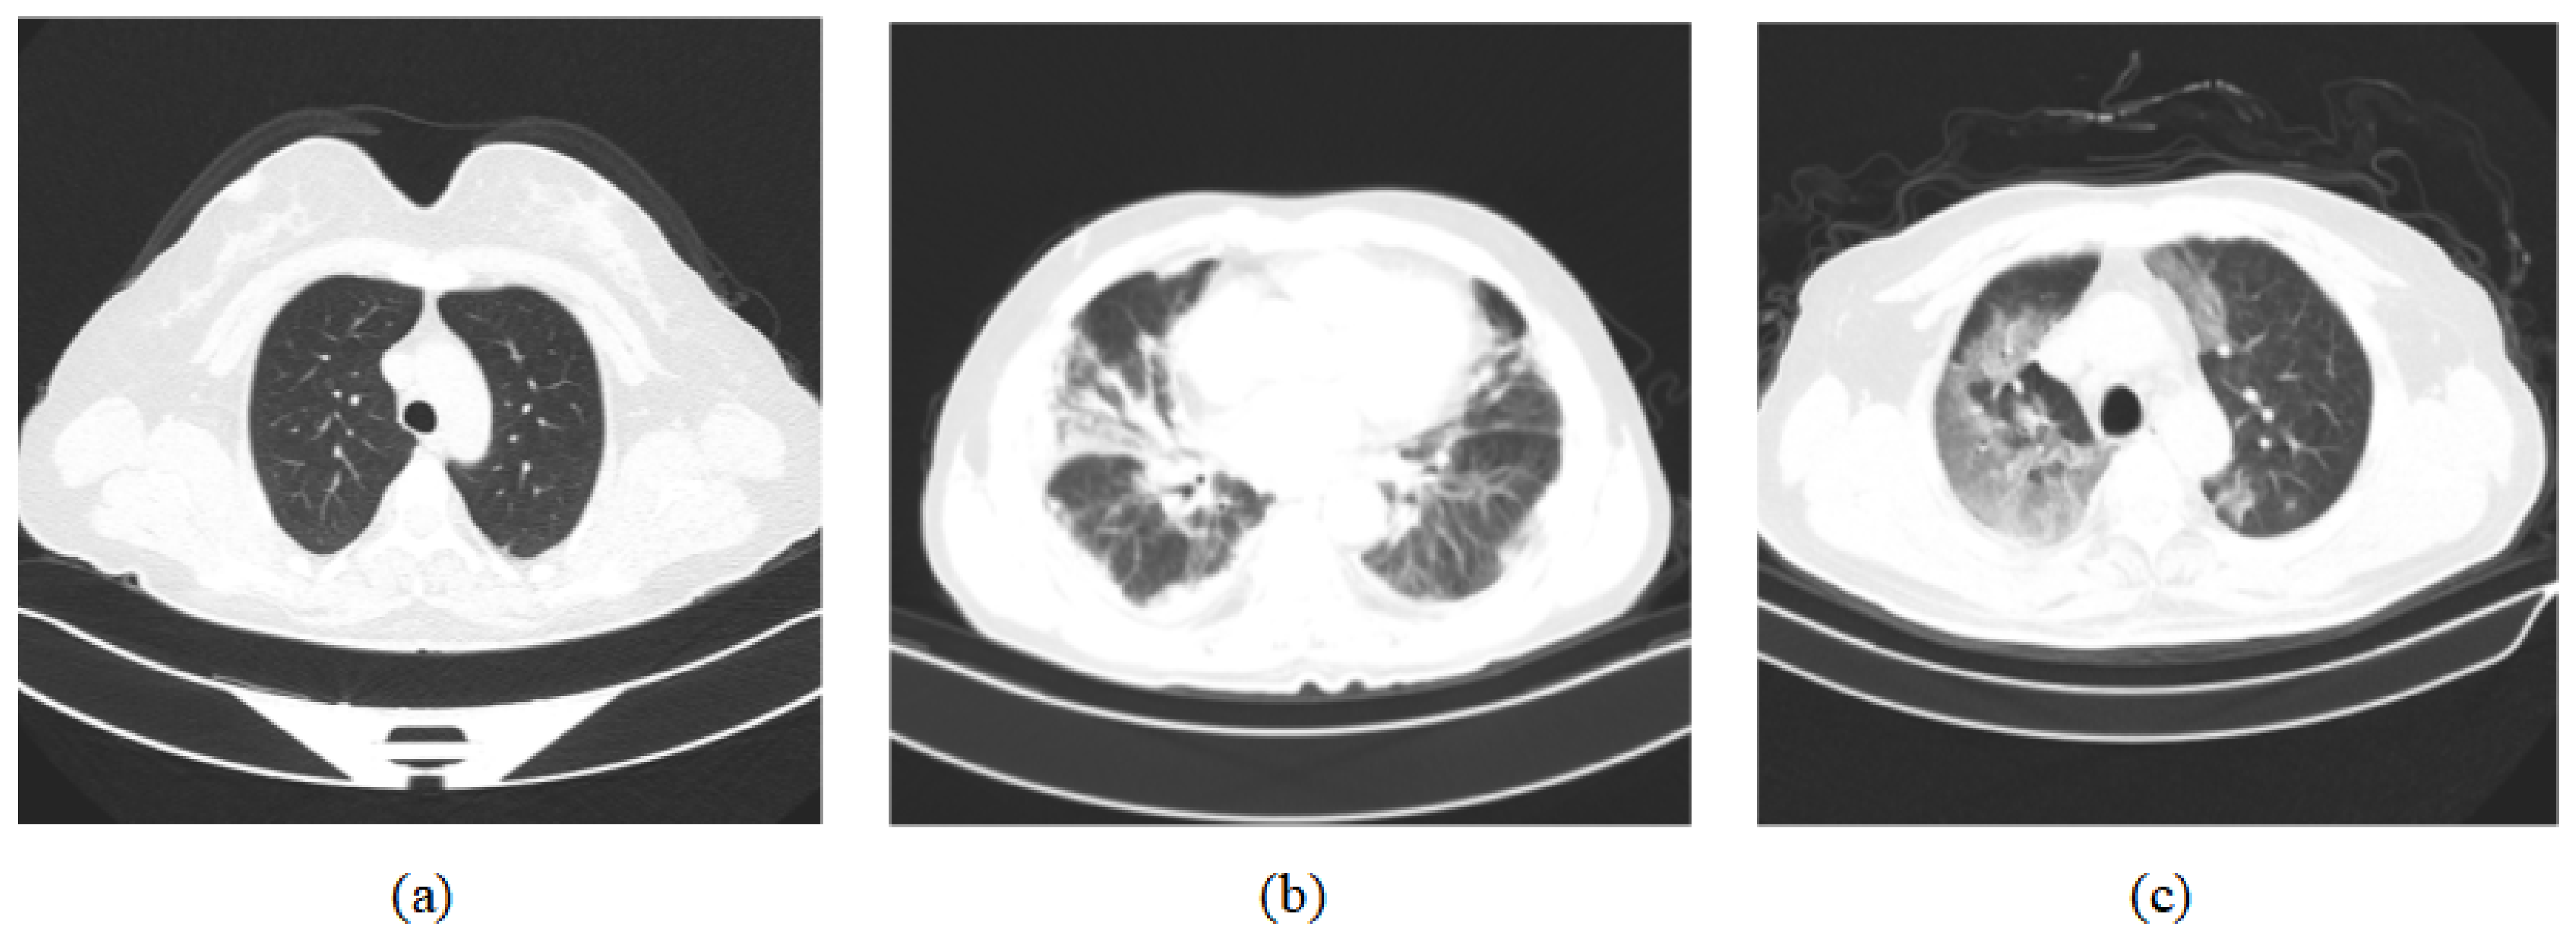

For the training and testing, we used two datasets, COVIDx CT-2 [11,12] and the integrated CT scan dataset [43]. The COVIDx CT-2 dataset has two diverse, large-scale datasets named COVIDx CT-2A and COVIDx CT-2B, and we chose COVIDx CT-2A. The patient cases collected in COVIDx CT-2A come from various organizations around the world, such as the China National Center for Bioinformation (CNCB), the National Institutes of Health Intramural Targeted Anti-COVID-19 (ITAC) Program, the Negin Radiology Medical Center, etc. The COVIDx CT-2A dataset contains 194,922 CT images (60,083 normal CT images, 40,291 images of patients with pneumonia, and 94,548 images of patients with COVID-19) from 3745 patients, with an image size of 512 × 512. In the integrated CT scan dataset, data are obtained from seven public datasets that contain 7593 COVID-19 images from 466 patients, 6893 normal images from 604 patients, and 2618 CAP images from 60 patients. In Figure 6, three categories of CT scan samples are illustrated, namely normal, COVID-19, and pneumonia. Among them, COVID-19 samples show a large number of GGO in the lungs. We divide the dataset into a training set, validation set, and test set in our experiments. For the COVIDx CT-2A dataset, we use 70% of the total samples for training, 10% of the total samples for validation, and 20% of the total samples for testing. For the integrated CT scan dataset, we use 60% of the total samples for training, 20% of the total samples for validation, and 20% of the total samples for testing. The specific distribution of the numbers is shown in Table 1.

Figure 6.

Dataset sample CT images [11,12]. (a) represents normal CT scan; (b) represents pneumonia CT scan; (c) represents COVID-19 CT scan.